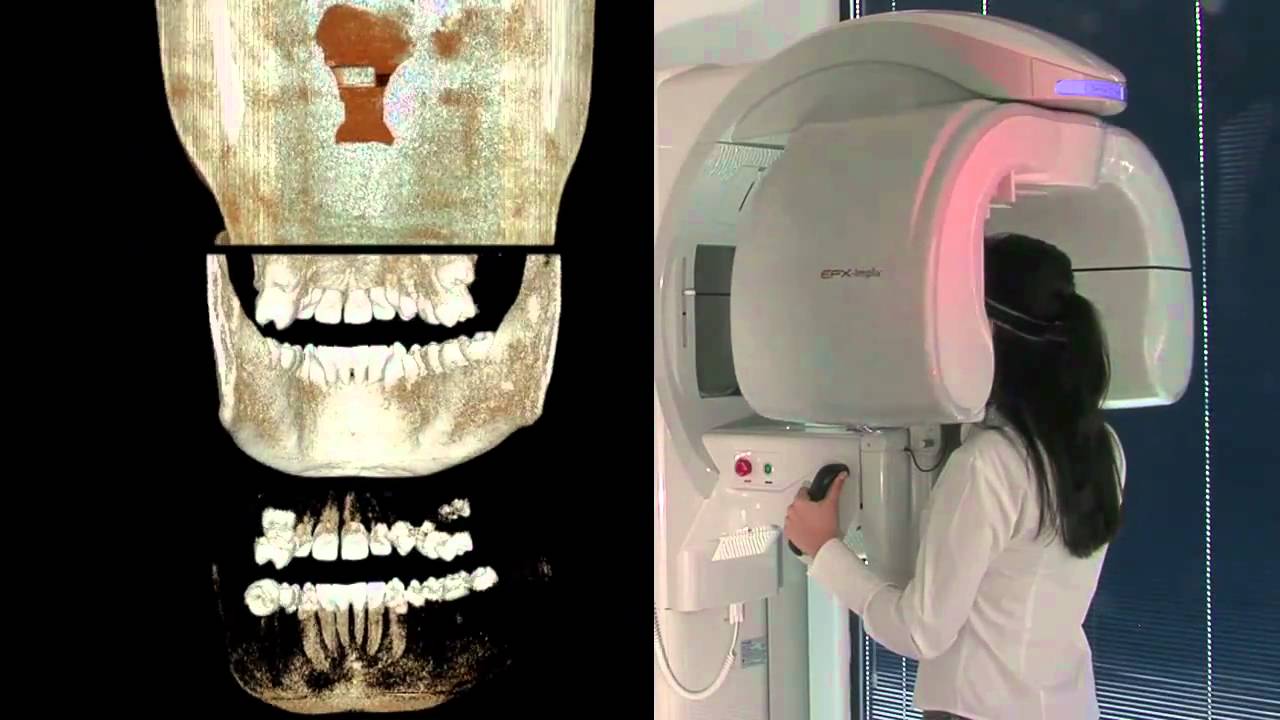

dabiatlante.com.brTomografia Cone Beam Na Radiologia Odontológica – Imagem Radiologia

dabiatlante.com.brTomografia Cone Beam Na Radiologia Odontológica – Imagem Radiologia

tomo3d.com.brTomografia Cone Beam Traz Benefícios Para Profissionais Da Odontologia

tomo3d.com.brTomografia Cone Beam Traz Benefícios Para Profissionais Da Odontologia